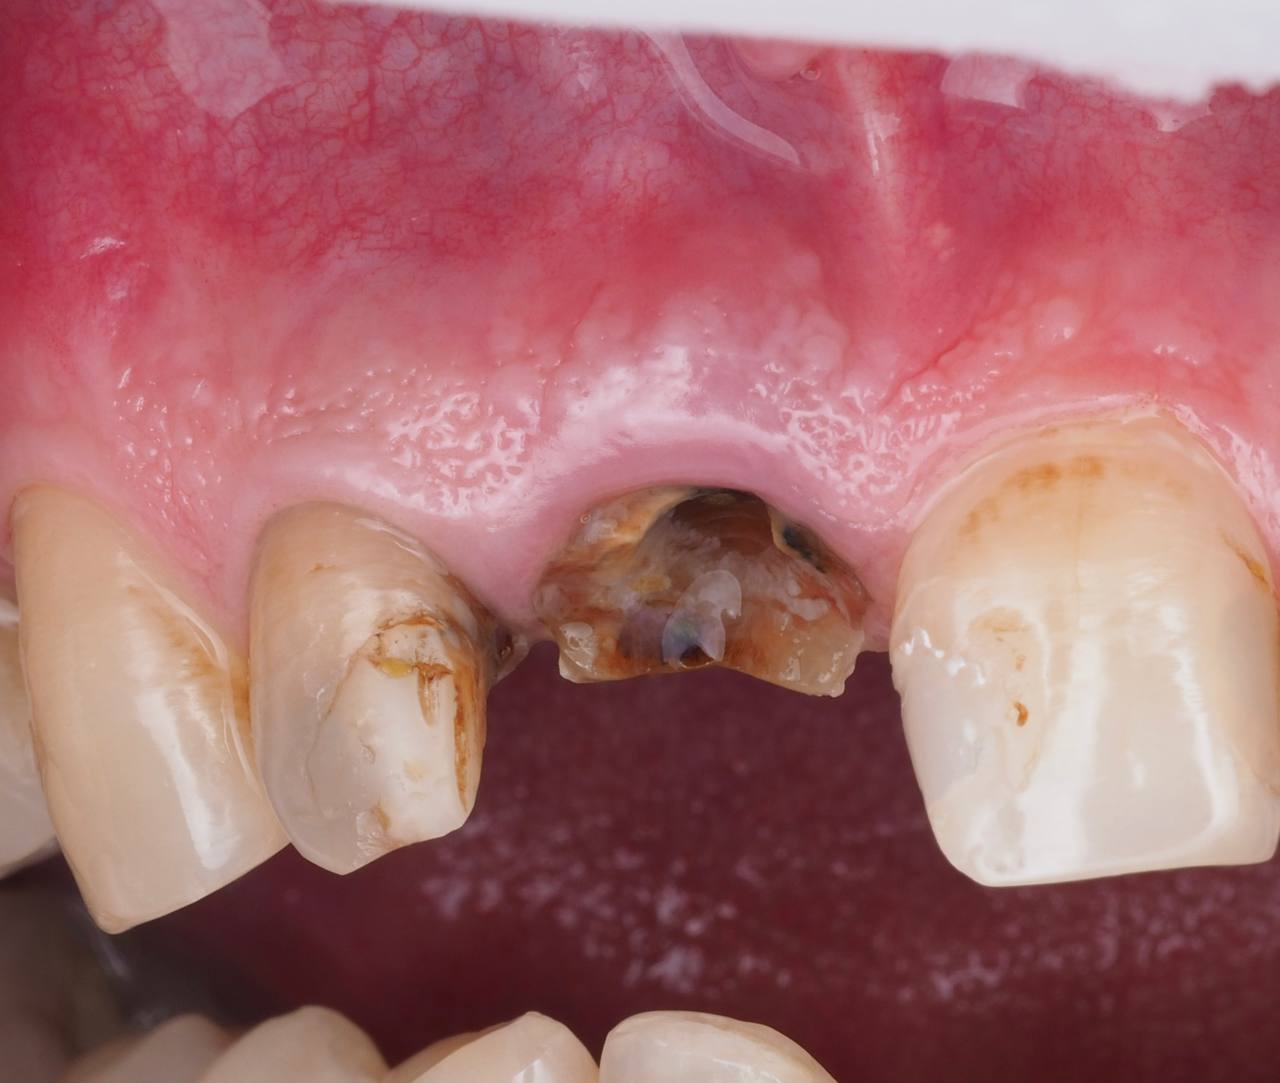

Одномоментная имплантация 1.1

AnyRidge, мультиюнит Octa, CCT, временная коронка